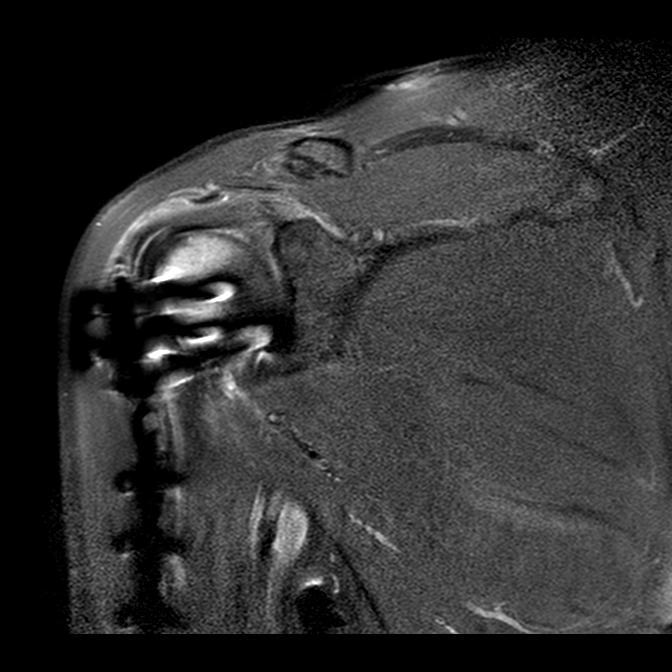

Hallo, heute war ich beim MRT, der Arzt meint, dass der Supraspinatus gereizt ist und auch die Sehe am Schlüsselbein. dies sei Abnutzung..ich denke, dass ist wohl eher Unfallfolge, oder (bin 54) Er meinte, mit der Plattenentfernung sollte man warten, bis alles stabiler und weniger gereizt sei. Mittlerweile habe ich weniger Bewegungseinschränkungen und der arm ist eingermassen alltagstauglich. Ich war sehr viel schwimmen und mache noch imme meine Physioübungen tgl. etwa 45 min bis 1 Stunde. Ist das vielleicht zuviel und ist es besser, die Plattenentferung erst nach einem Jahr anzudenken oder eben auch schon nach 7 Monaten. Mir ist bewusst, dass sich dafür noch mal einen neunen Röntgenbefund brauche. Das Schulterblatt steht wieder besser, steht aber noch ab. Den Arm bekomme ich zum Ohr, aber noch nicht weiter nach hinten. Auf dem Rücken kann ich beide Hände zusammenführen, sowohl von oben wie auch von unten mit dem kaputten Arm. Ich mache viele Dehnübungen und habe das Gefühl, dass dies viel bringt. Was empfehlt Ihr? lg anna -

Hallo, heute war ich beim Neurologen wegen der Fragestellung einer Plexusläsion in Zusammenhang mit meiner subcapitalen Humerusfraktur. Elektrophysiologisch war alles unauffällig. Nun geht es weiter mit einem MRT. Nach wie vor habe ich rechts eine scapula alata mit parese Musculi rhomboidei. Innenrotation rechts KG4, Parese Armbeuge KG4, Anteversion KG4, was auch immer das bedeutet. Fakt ist, dass sich die Schulter instabil anfühlt, ich nach wie vor recht schlecht schalfe. wenn ich die Arme im 45 grad Winkel nach vorne an die Wand drücke, steht der rechte Unterarm immer schief nach innen, Aussenrotation ist relativ schwer, Schulter kommt bei über 90 Grad nach oben und das Schulterblatt steht hinten ab. Alles in allem geht es aber besser. Brustschwimmen und Rückenschwimmen geht gut, Auto- und Fahhradfahren auch. Bewegungen nach vorne oben sind auch Dauer mühsam. Die Aussenrotation übe ich verstärkt und widme meinem Arm jeden Tag eine Stunde Training nach Anleitung meiner Physios; lass mir alle Übungen immer für zu Hause mit Tubes und Gewichten "übersetzen". Was mich nach wie vor irritiert ist, dass meine Arme unterschiedlich stehen. Das sieht man an der Ellenbogeninnenseite, die kaputte Seite schaut mehr nach innen. Welche Schwimmarten sind besonders geeignet, gibt es sonstige Tipps, für das, was noch nicht gut funktioniert? lg Anna -